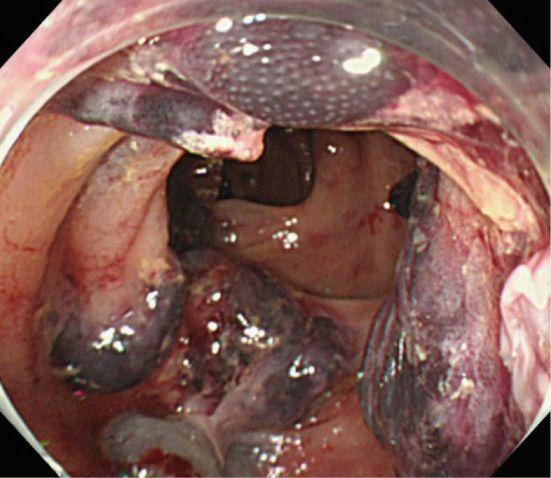

Рисунок 3. AL-амилоидоз у 80-летнего мужчины [17].

Экстренная колоноскопия, проведенная пациенту 80 лет с гематохезией и поражением сердца, выявила множественные подслизистые гематомы толстой кишки.